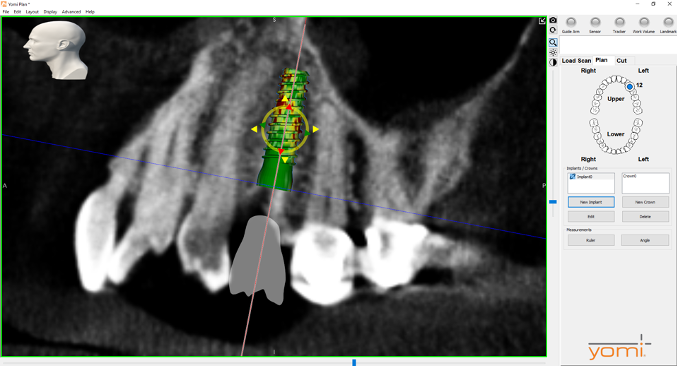

After a CBCT scan (Figure 3) and a digital impression were obtained for diagnosis and treatment planning, the DICOM file from the CBCT scan and the STL file from the digital impression were merged in a treatment planning software application for evaluation. A virtual crown was then created to facilitate a restoration-driven approach. The vital structures and osseous anatomy were identified, and the implant position was planned virtually (Figure 4 and Figure 5).

(4.) Digital plan of the virtual implant.

Figure 4

(5.) Digital plan of the virtual implant.

Figure 5